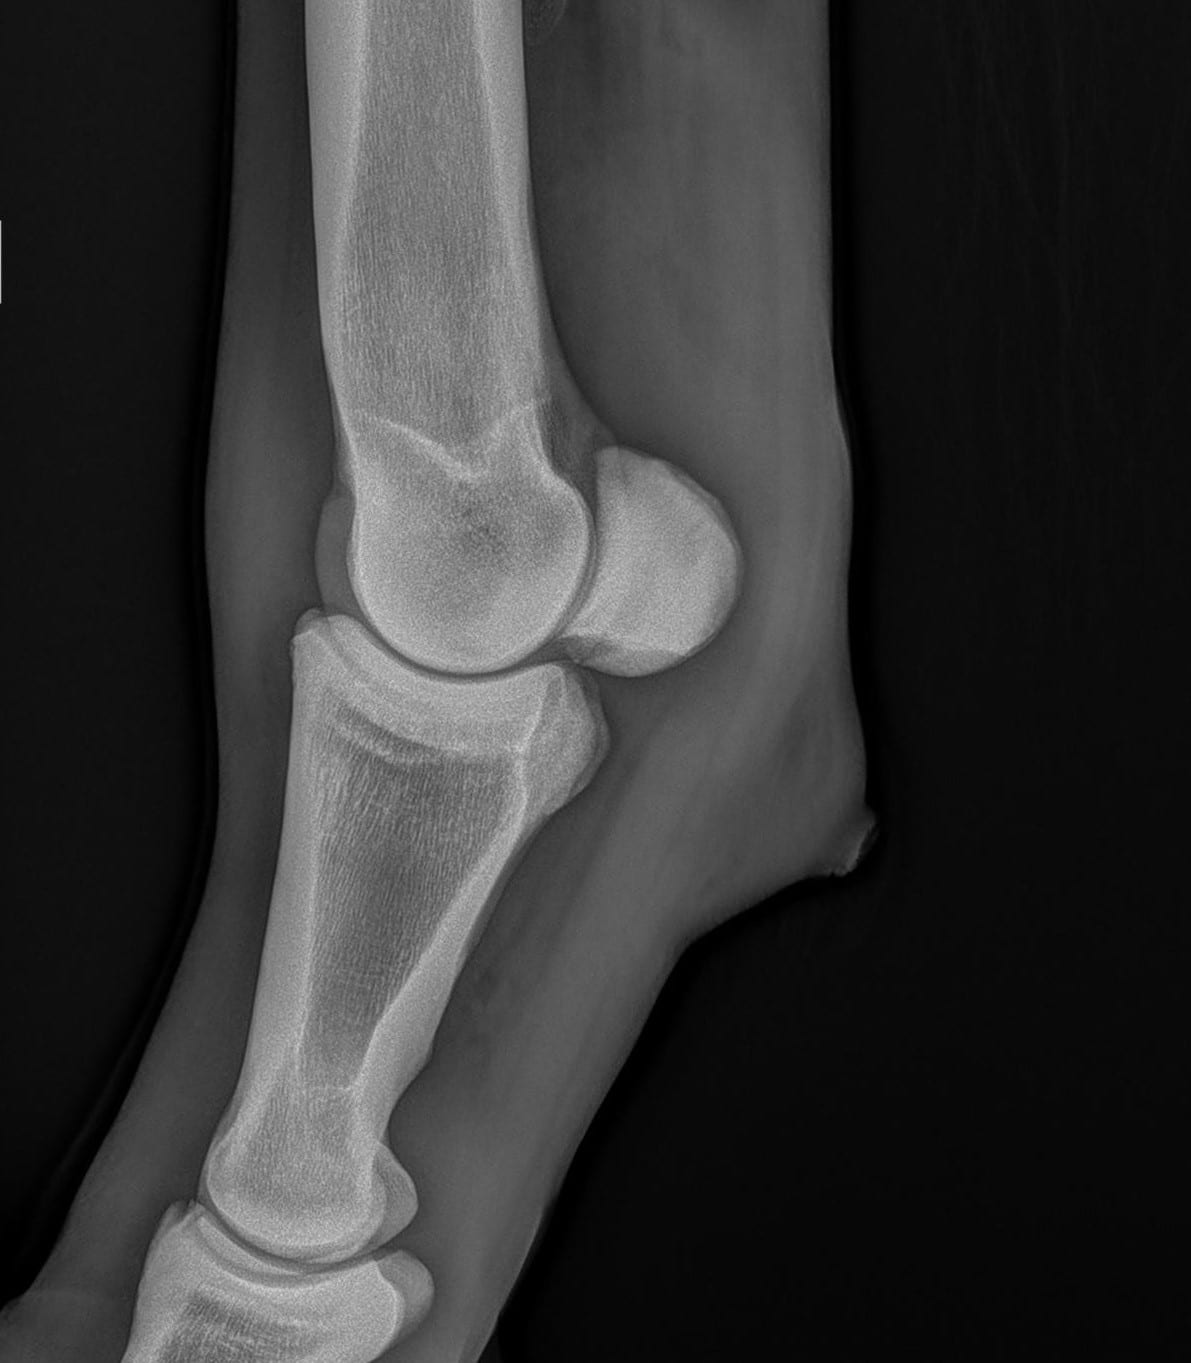

Bij onderzoek naar een stoornis aan het bewegingsapparaat wordt röntgen intensief gebruikt. Röntgenonderzoek laat veranderingen zien zoals kreupelheid, fracturen, botontstekingen en standsafwijkingen. Ook aanhechtingsproblemen van pezen en banden met botafwijkingen zijn in beeld te brengen. Daarnaast wordt röntgenonderzoek gebruikt bij problemen aan het hoofd en het gebit. Bij onderzoek naar problemen aan de luchtwegen kunnen röntgenfoto’s gebruikt worden voor het stellen van een diagnose. Voor een röntgenonderzoek wordt het paard onder lichte verdoving gebracht, zodat deze keurig stil staat en minder onder de indruk is van alle apparatuur. Om problemen in beeld te brengen zijn vaak meerdere röntgenfoto’s van dezelfde locatie noodzakelijk.